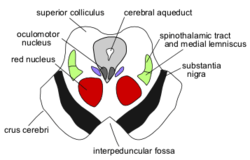

The midbrain comprises the tectum (or corpora quadrigemina), tegmentum, the cerebral aqueduct (or ventricular mesocoelia or "iter"), and the cerebral peduncles, as well as several nuclei and fasciculi. Caudally the midbrain adjoins the metencephalon (afterbrain) (pons and cerebellum); while rostrally it adjoins the diencephalon (thalamus, hypothalamus, etc.). The midbrain is located below the cerebral cortex, and above the hindbrain, placing it near the center of the brain.[3]

The cerebral peduncles are paired structures, present on the ventral side of the cerebral aqueduct, and they further carry tegmentum on the dorsal side and cresta or pes on the ventral side, and both of them accommodate the corticospinal tract fibres, from the internal capsule (i.e., ascending + descending tracts = longitudinal tract.) the middle part of cerebral peduncles carry substantia nigra (literally "Black Matter"), which is a type of basal nucleus. It is the only part of the brain that carries melanin pigment.

Between the peduncles is the interpeduncular fossa, which is a cistern filled with cerebrospinal fluid. The oculomotor nerve comes out between the peduncles, and the trochlear nerve is visible wrapping around the outside of the peduncles. The oculomotor is responsible for pupil constriction (parasympathetic) and certain eye movements.[6]

- A horizontal (transverse) cross-section at the level of the superior colliculus shows the red nucleus, the nuclei of the oculomotor nerve (and associated Edinger-Westphal nucleus), the cerebral peduncles or crus cerebri, and the substantia nigra.[7]

- A horizontal (transverse) cross-section at the level of the inferior colliculus still shows the substantia nigra. Also apparent are the trochlear nerve nucleus, and the decussation of the superior cerebellar peduncles.[8]

- Both sections will show the cerebral aqueduct, which connects the third and fourth ventricle and the periaqueductal gray.[9]